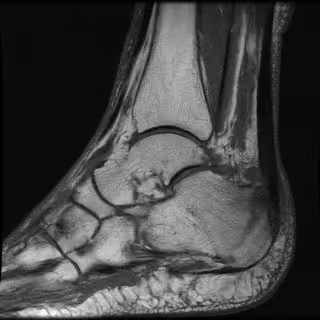

En el artículo 'Identification of fracture zones and its application in automatic bone fracture reduction', publicado en la revista Comput Methods Programs Biomed, los expertos jiennenses han confirmado el éxito de este método en casos de fractura por impacto en huesos de tobillo, que suelen ser las lesiones de mayor complicación por la cantidad de piezas afectadas.

El método identifica las heridas de una manera exacta partiendo de una imagen obtenida por tomografía axial computarizada (TAC), una prueba diagnóstica de rayos X que permite observar el interior del organismo en forma de cortes transversales o tridimensionales. Así, se puede conocer 'a priori' y de forma precisa si se observan sólo partes óseas o también hay músculos, tendones u otro tipo de tejidos blandos que no se diferencian en una radiografía convencional.

El enfoque que se muestra en este artículo se ha aplicado con éxito en diferentes casos de traumas en el área del tobillo, una de las más complicadas en cirugía traumatológica. El sistema ha calculado de manera precisa en todos los casos clínicos probados que no existían solapamientos o espacios visibles entre los fragmentos.